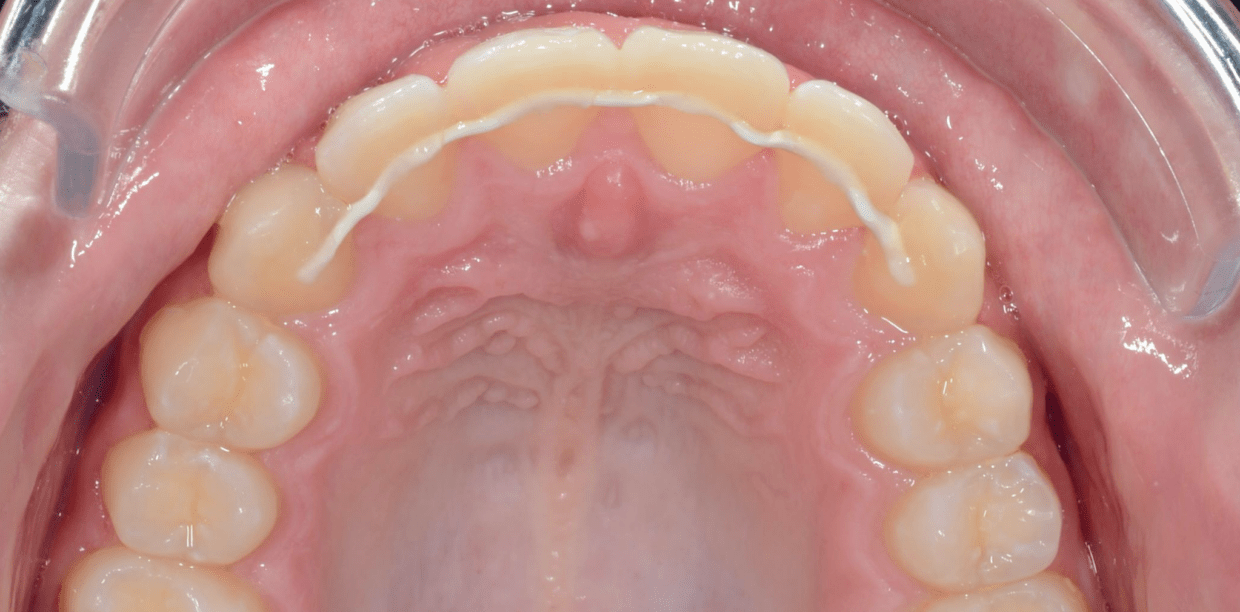

Cas cliniques

Simple - White

Simple - White

Simple - White